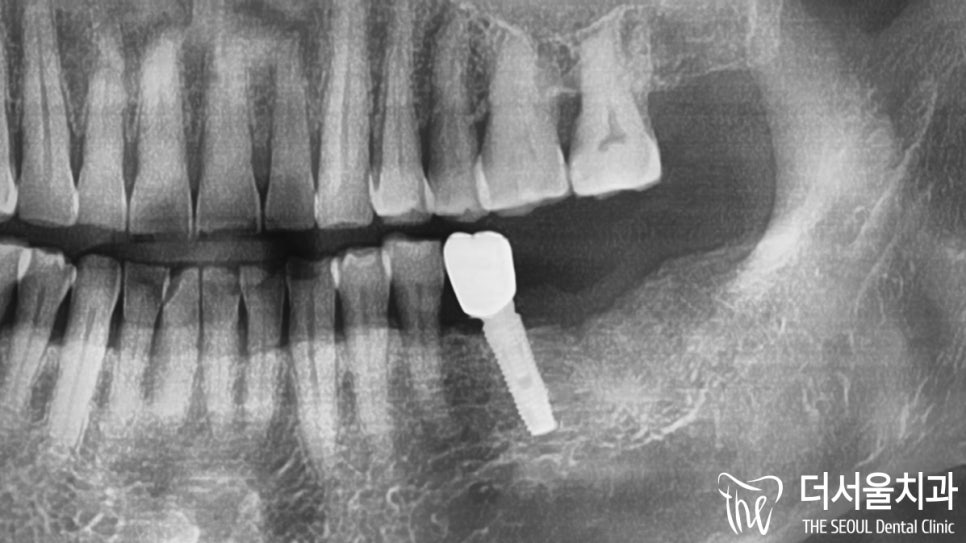

파노라마에서 확인해보니

아래 37번 치아 주변으로

골소실 및 염증이 나타나 있었습니다.

자세히 보면 치관 부위에

파절이 나타난 것으로 확인이 되는데요.

그로인해 염증이 발생하였고

오랜시간 방치를 하면서

병소가 점점 퍼지게 된 것입니다.